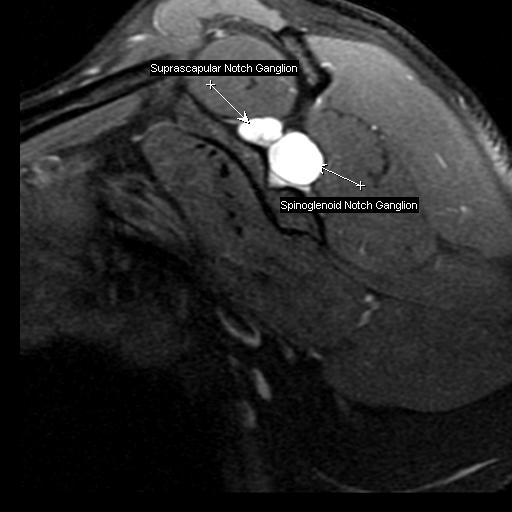

Figure 2 for case Notch ganglion cysts

Figure 2